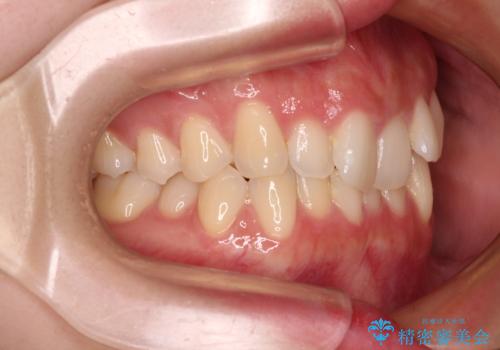

前歯が隠れるほどのデコボコをインビザライン矯正できれいに整える

- 前歯のデコボコを気にして来院された患者様です。

全体的にデコボコが多く、特に下の前歯は隠れてしまうほどの状態でした。

左右ともに奥歯の咬み合わせが理想的な位置にあったこともあり、患者様のご希望通り、インビザラインにて矯正治療を行うこととしました。